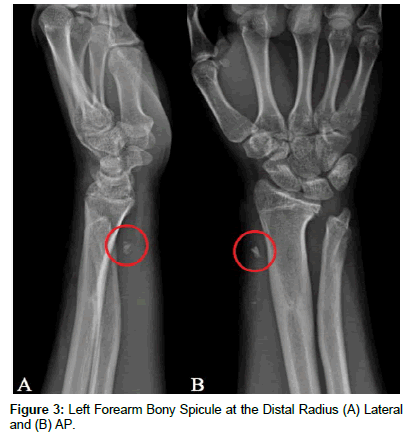

[04/11/2016] The patient again presented to clinic with a recurrence of the abscess and one week of progressively worsening swelling and erythema at the left distal radius; he had otherwise been asymptomatic during the interim following his hospital discharge and off antibiotic therapy for six weeks. Serosanguinous fluid aspirated from the abscess grew 2+ Staphylococcus Aureus (MSSA) with a similar antibiotic susceptibility profile as had been previously determined. Plain films of the left forearm revealed the presence of a bony spicule in the soft tissue at the lateral aspect of the distal radius (Figure 3); it is suspected that the fragment is a result of possible early consolidation of the heterotopic ossification previously noted. The patient and his parents opted to pursue surgical wound debridement and excision of the bony fragment. [05/09/2016] Surgical exploration of the left wrist first extensor compartment revealed notable inflammatory changes and synovitis, with thickening of the sheath. Additionally, the spicule previously noted on x-ray alongside necrotic fatty tissue was identified and subsequently removed. Acute osteomyelitis of the bone fragment was diagnosed secondary to histologic features of neutrophilic granulocyte infiltrate and necrotic bone tissue. The patient was discharged on Cephalexin antibiotic therapy one gram by mouth daily for 28 days. He has not had a recurrence of the abscess over the past year and has been doing well, without the need for additional antibiotic therapy or surgical intervention.